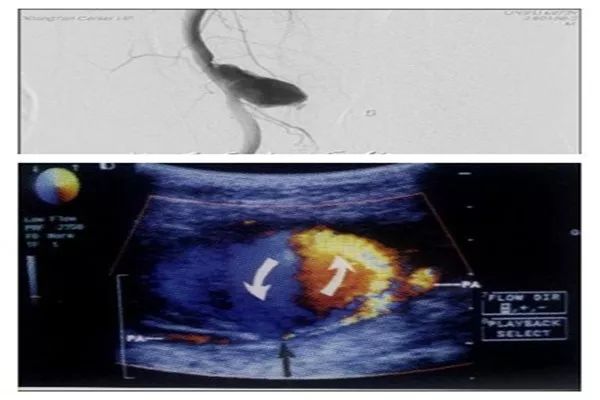

4. 假性动脉瘤

经皮穿刺以后动脉局部出血、血液通过动脉壁裂口进入血管周围策划,形成一个或多个腔隙(瘤腔)。病理表现为收缩期动脉血液经过载瘤动脉与瘤腔之间的通道(瘤颈部)流入瘤腔内,舒张期血流回流到动脉内。

处理假性动脉瘤的方法有超声引导下注射凝血酶、超声引导下局部压迫、置入弹簧圈、外科手术修补。假性动脉瘤发现得越早,采用局部压迫的处理方法越好。

图5. 假性动脉瘤影像。